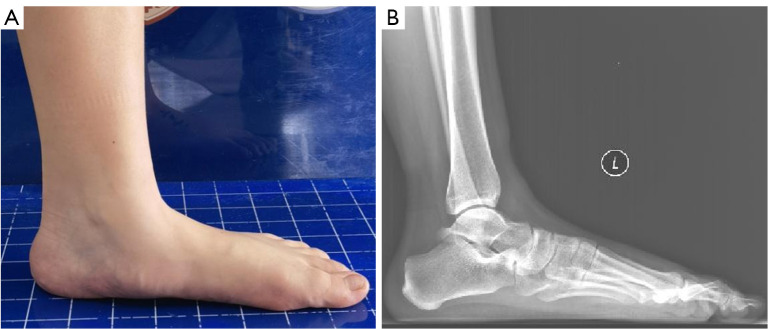

Background: Flexible flat foot is a relatively common disease treated by foot and ankle surgery, and subtalar arthroereisis (STA) has gradually become favored by foot and ankle surgeons due to its advantages. However, which sinus tarsi implant is optimal remains controversial. The purpose of this study was to compare the biomechanical outcomes of two types sinus tarsi implants of different sizes via finite element analysis.

Methods: A finite element model of pediatric flexible flatfoot deformity was established in which virtual surgery of STA was simulated. Boundary and loading conditions were assumed from the data of previous finite element analysis study. The corrective ability in talar-first metatarsal angle, talonavicular coverage angle, calcaneus pitch angle, and arch height were compared and analyzed. The indexes of plantar stress distribution, the peak von Mises of medial and lateral columns, and strain of the medial ligaments were also compared and analyzed.